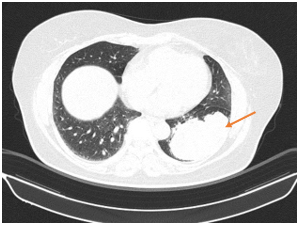

- CLVT lồng ngực – ổ bụng:

Hình 2. Thuỳ dưới phổi trái có khối đặc lớn, bờ thuỳ múi không đều, kích thước ~ 89x545mm xâm lấn màng phổi lân cận

Hình 3. Đỉnh phổi phải có khối bờ thuỳ múi tua gai kích thước 35x36mm, theo dõi xâm lấn màng phổi thành lân cận.